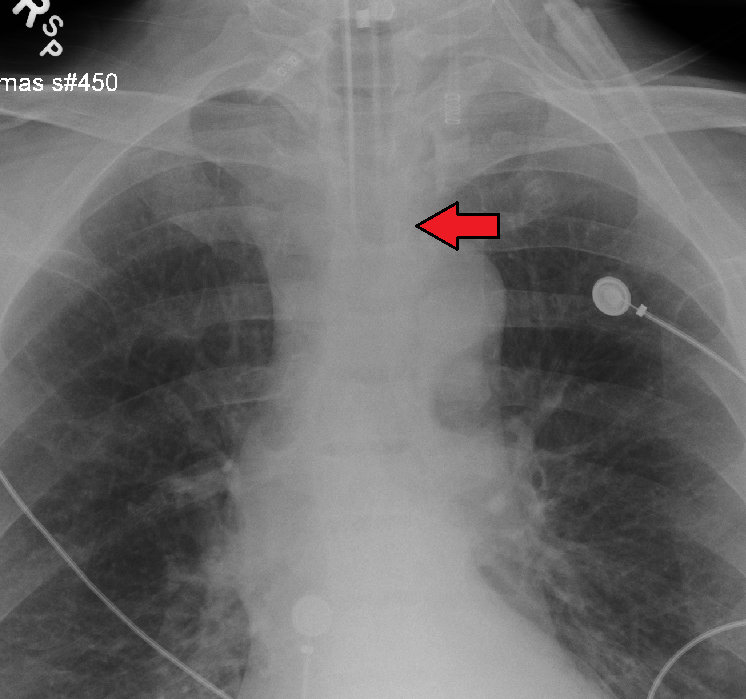

기관 튜브가 제 위치에 있는지 확인하기 위해 여러 방법을 사용한다. 캡노그래피는 기관 내 튜브 설치 확인을 위한 골드 스탠다드로 사용되고 있다. 튜브의 위치는 흉부 X선 촬영으로도 확인할 수 있는데, 기관 분기부에서 약 2cm 위에 위치하는 것이 이상적이다.

적절한 위치에 있는 기관 튜브의 원위단은, 기관 분기부에서 약 2cm 위에 위치하며, 이는 흉부 X선 촬영으로 확인할 수 있다. 기관이 기관 분기부보다 너무 깊이 들어가면, 기관 튜브의 선단이 우측 주 기관지 안으로 들어갈 수 있다 ('''한쪽 폐 삽관'''이라고 불린다). 이 상황에서는, 좌측 폐가 환기에 관여할 수 없게 되어, 환기 혈류 불균형에 의한 저산소혈증에 빠질 수 있다.

적절하게 위치한 기관 튜브의 팁은 쇄골 사이의 전후면 흉부 방사선 사진에서 중간 기관에 위치한다. 튜브의 적절한 직경은 약 25cm 수압에서 약간의 누출이 발생하는 직경이다. 기관 내 튜브의 적절한 내경은 아이의 새끼손가락과 대략 같은 직경으로 추정된다. 기관 내 튜브의 적절한 길이는 아이 입의 모서리에서 귓구멍까지의 거리를 두 배로 하여 추정할 수 있다. 생후 1년 이상 된 정상적으로 영양 상태가 좋은 어린이의 경우, 기관 내 삽관에 적절한 직경과 깊이를 추정하기 위해 두 가지 공식이 사용된다. 튜브의 내경(mm)은 (환자의 나이 + 16) / 4이고, 적절한 삽입 깊이(cm)는 12 + (환자의 나이 / 2)이다.